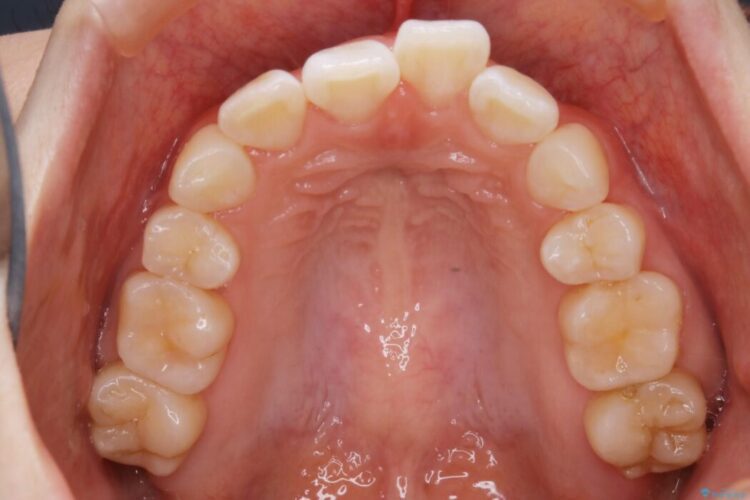

以前治療した抜歯矯正から後戻りをしてしまった歯列のがたつきを再矯正したいとのことで来院されました。

元々中学生から高校生にかけてワイヤー装置を用いた矯正治療をされた患者様でした。

大人になるにつれてライフスタイルの変化が生じ、歯が元の位置に戻らないように保定するためのリテーナーを継続使用することが難しくなったことから、歯列にがたつきが目立つようになったのでもう一度矯正治療をしたいとのご希望でした。

既に上下左右の4番目の歯が抜歯されているため、今回のケースでは非抜歯による歯の移動のみで矯正をしなければならず、難易度が高いものになりました。